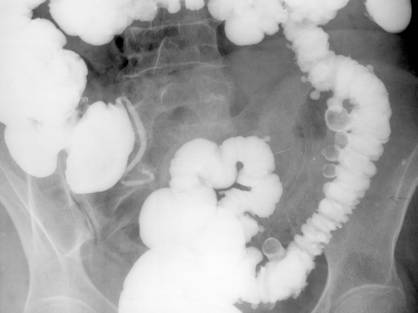

Fig. 46 – Boala Crohn (triada Bodart)

1. Boala Crohn (ileita terminala)

Boala imbraca doua aspecte clinico-radiologice:

- tabloul nestenozant - ingrosarea mucoasei

- aspect pseudopolipoid cu spiculi marginali si contur flu (hipertrofia placilor Peyer);

- tabloul stenozant - segmentul prevalvular ingust, tubular, fara relief;

- incontinenta valvulei ileocecale (aspect de cioc de rata - semnul Fleishner);